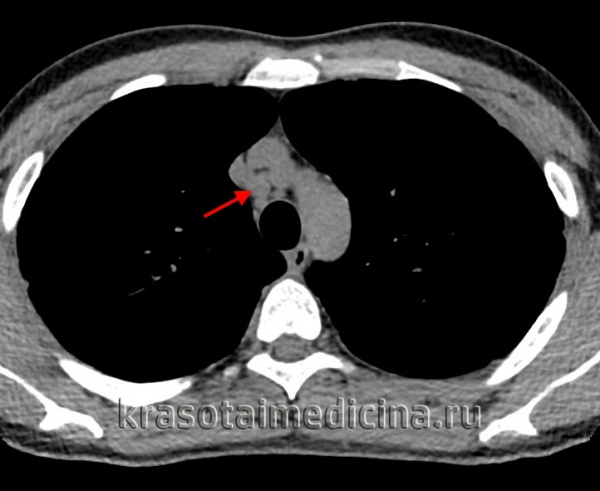

Характерные изменения при саркоидозе выявляются при рентгенографии легких, в ходе КТ или МРТ легких - определяется опухолевидное увеличение лимфоузлов, преимущественно в корне, симптом «кулис» (наложение теней лимфоузлов друг на друга); очаговая диссеминация; фиброз, эмфизема, цирроз легочной ткани. У более половины пациентов с саркаидозом определяется положительная реакция Квейма – появление багрово-красного узелка после внутрикожного введения 0,1—0,2 мл специфического саркоидного антигена (субстрата саркоидной ткани больного).

КТ органов грудной клетки. Множественные типичные саркоидозные очаги субмиллиметрового диапазона с диффузным распространением